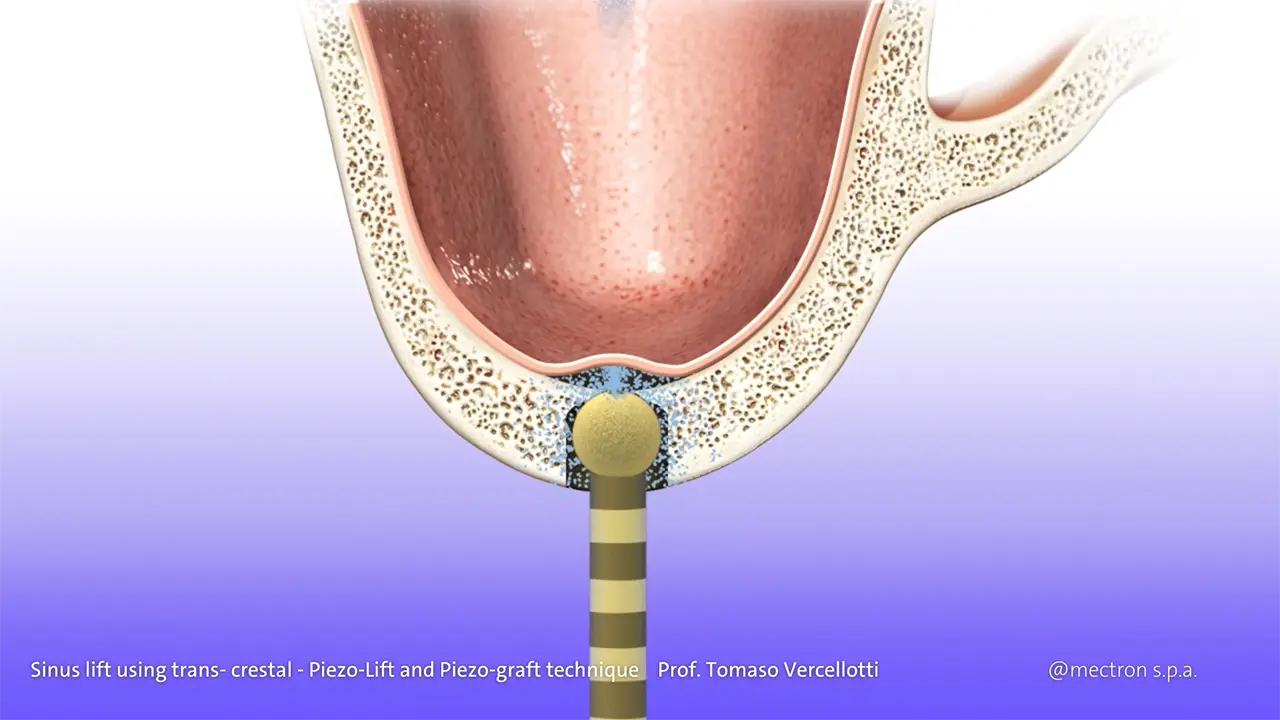

PIEZOSURGERY® Sinus lift

Prof. Tomaso Vercellotti

Prof. Tomaso Vercellotti

Sinus lift using trans- crestal approach – Piezo-Lift and Piezo-graft technique